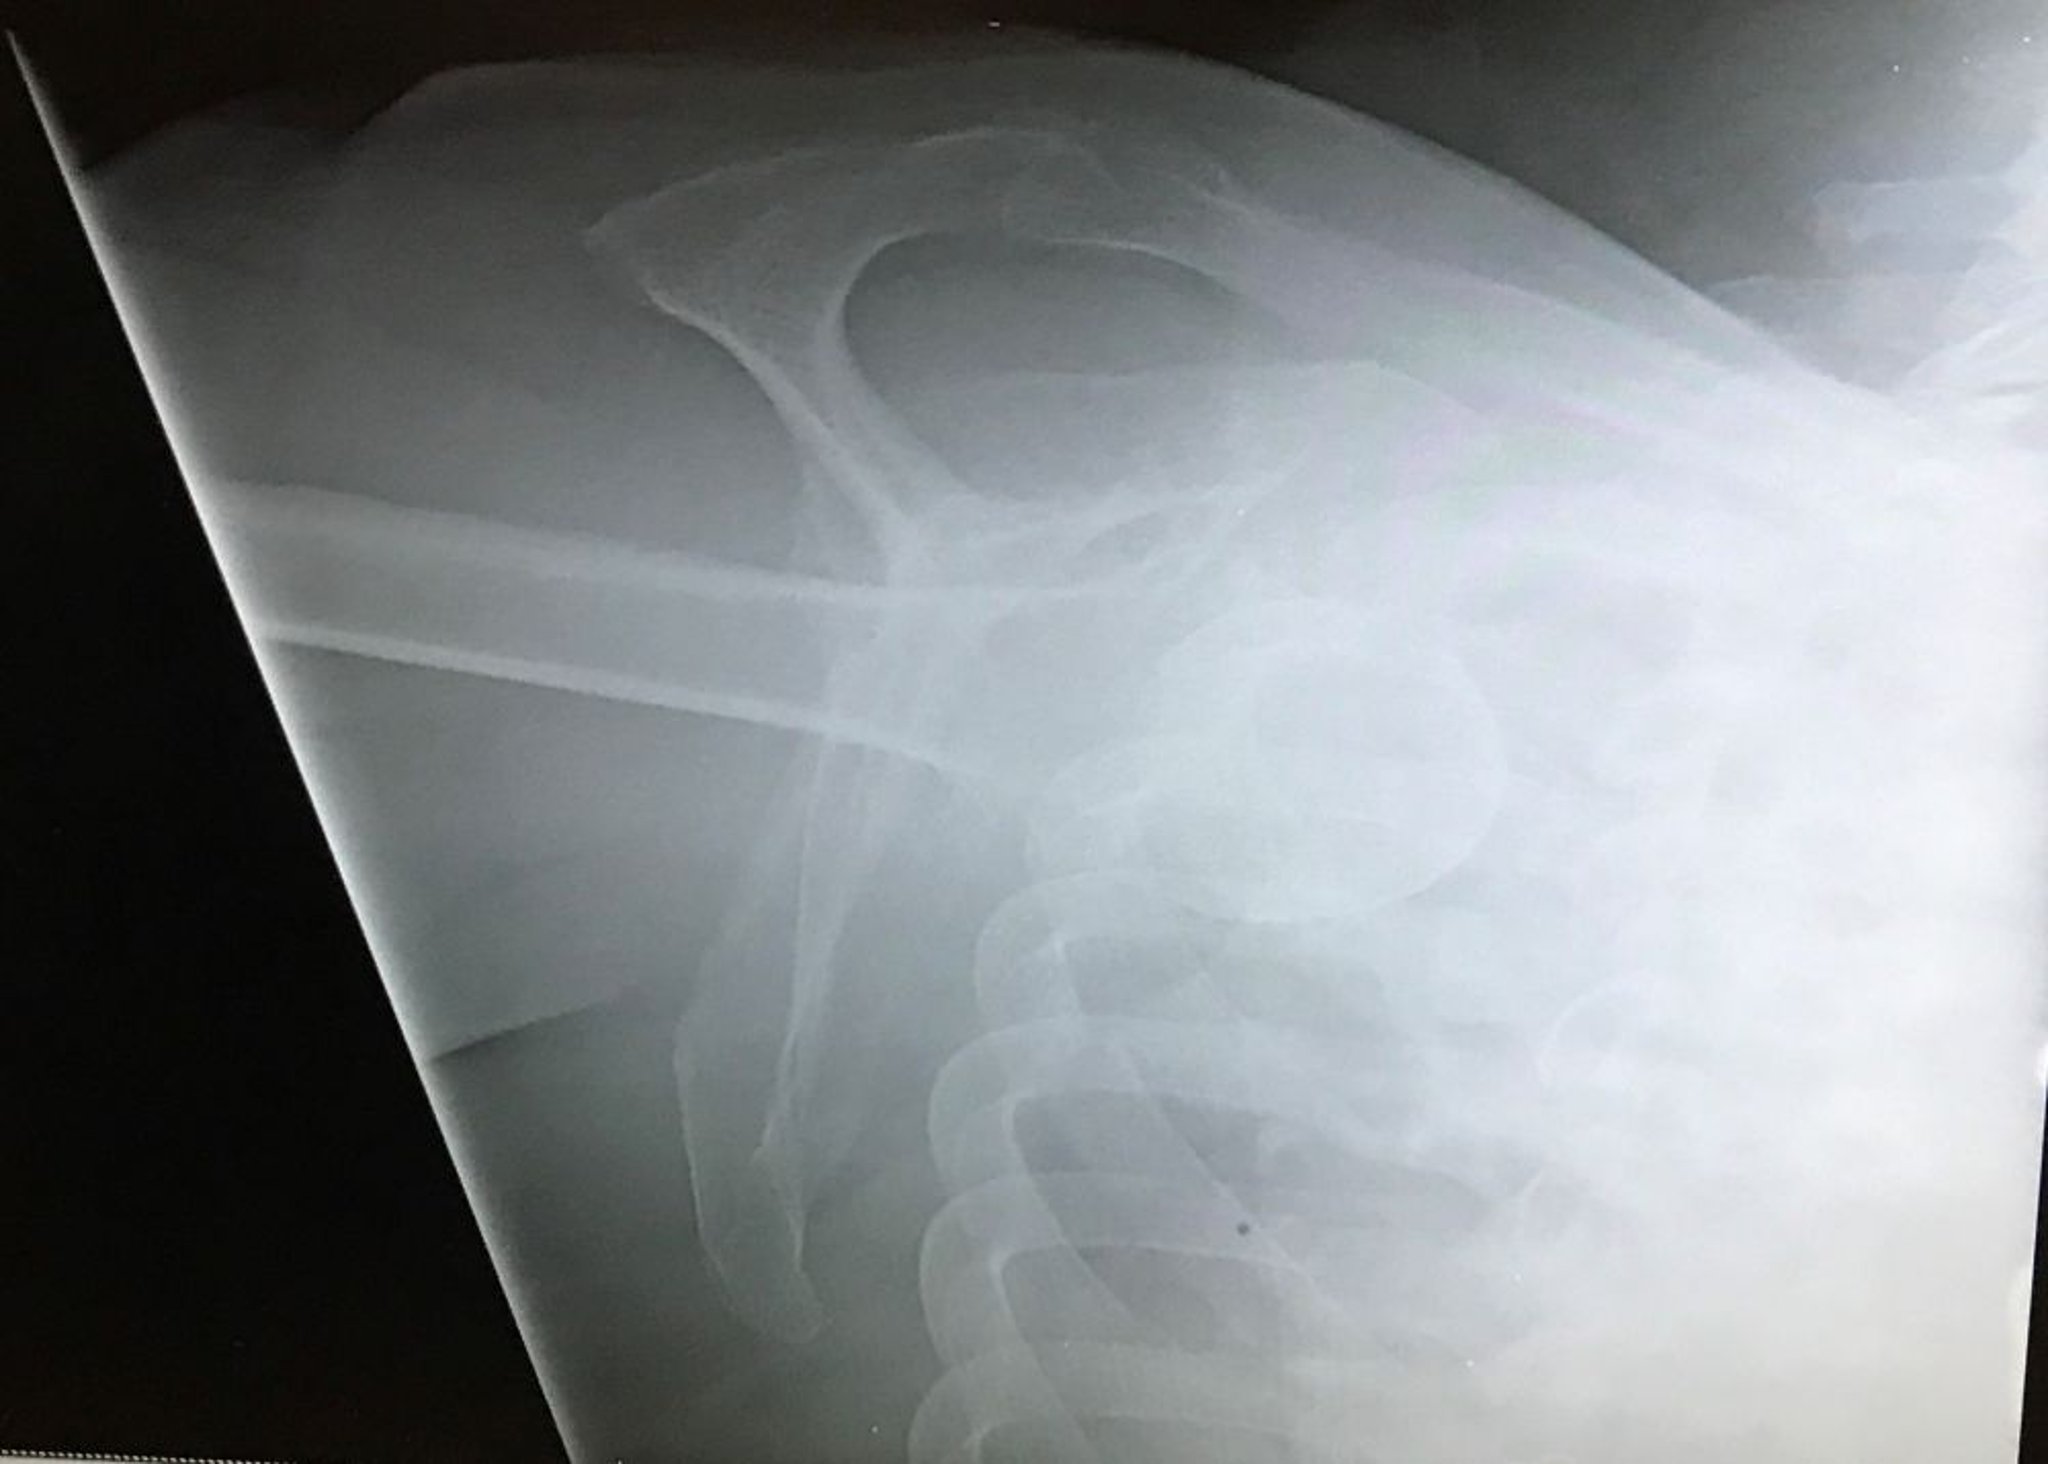

Luxation inférieure de l'épaule

Cette vue en Y de l'épaule montre la tête humérale inférieure à la fosse glénoïde avec l'extrémité en direction céphalique, indiquant une luxation glénohumérale inférieure (luxatio erecta).

Image courtoisie de Danielle Campagne, MD.